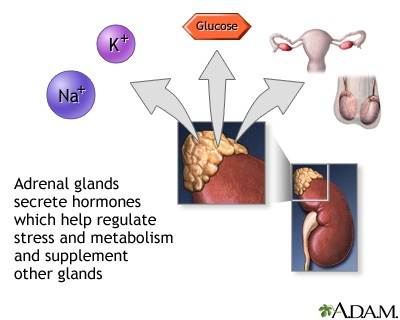

Pheochromocytoma is a rare tumor of adrenal gland tissue that typically arises from the adrenal gland. It results in the release of too much epinephrine and norepinephrine, which are hormones that control heart rate, metabolism, and blood pressure.

Pheochromocytoma may occur as a single tumor or as more than one growth. It usually develops in the center (medulla) of one or both adrenal glands. The adrenal glands are two triangle-shaped glands. One gland is located on top of each kidney. In rare cases, a pheochromocytoma occurs outside the adrenal gland. When it does, it is usually somewhere else in the abdomen.

Adrenal glands